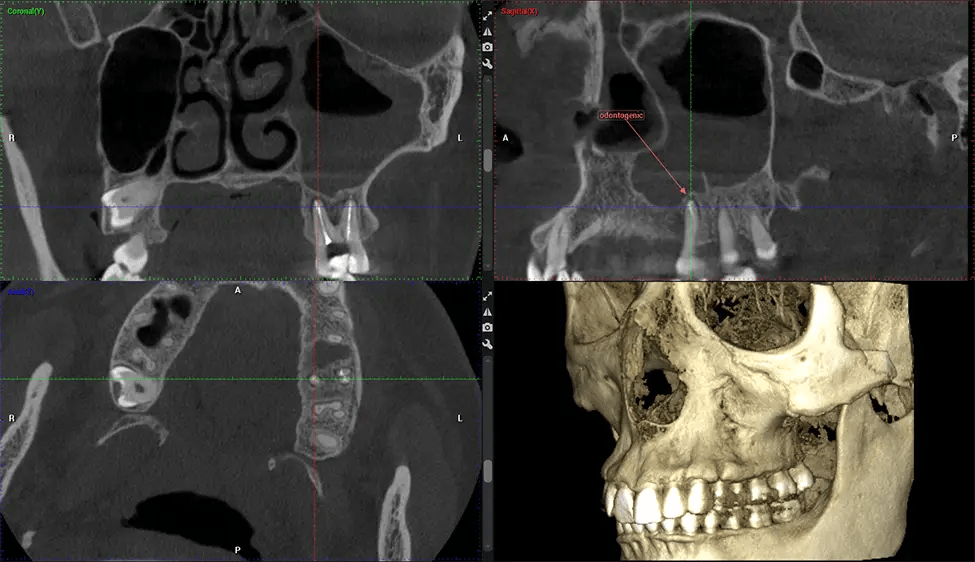

This 3D scan, called cone beam computed tomography, gives your dentist a more complete image of your oral anatomy and disease processes than a traditional X-ray. Unlike conventional X-rays, which capture a 2D image of your mouth from various angles, a 3D scan takes multiple digital X-rays for one image. It provides a complete view of your jaw, teeth, nerves, and soft tissues. This enhanced view allows dentists to detect minor issues not visible in traditional 2D scans, such as impacted wisdom teeth or bone fractures in the sinus cavity.

There are many benefits to using CBCT technology, especially compared to the traditional 2D X-ray format. One of the most significant advantages of CBCT scans is that they provide much more information than traditional X-rays. A scan lets your dentist see images from all angles of your jaw and mouth, including your sinuses, nasal cavity, cheekbones, and other surrounding areas. This added information helps your dentist craft a comprehensive treatment plan that addresses all aspects of your oral health.

Another significant benefit is that 3D imaging provides more precise images of your bone structure. These images are more detailed, providing you with a more accurate diagnosis. An accurate diagnosis means better treatment for you.

After the scanning process, the captured X-ray images are processed by the CBCT software, which applies algorithms to reconstruct a detailed 3D image of the scanned area. The software compiles these individual X-ray images and creates a digital 3D representation of the patient’s anatomy. The reconstructed 3D CBCT image can be viewed and analyzed by the dentist or radiologist. This image can be manipulated, rotated, and zoomed in or out to examine specific structures and evaluate the patient’s condition.